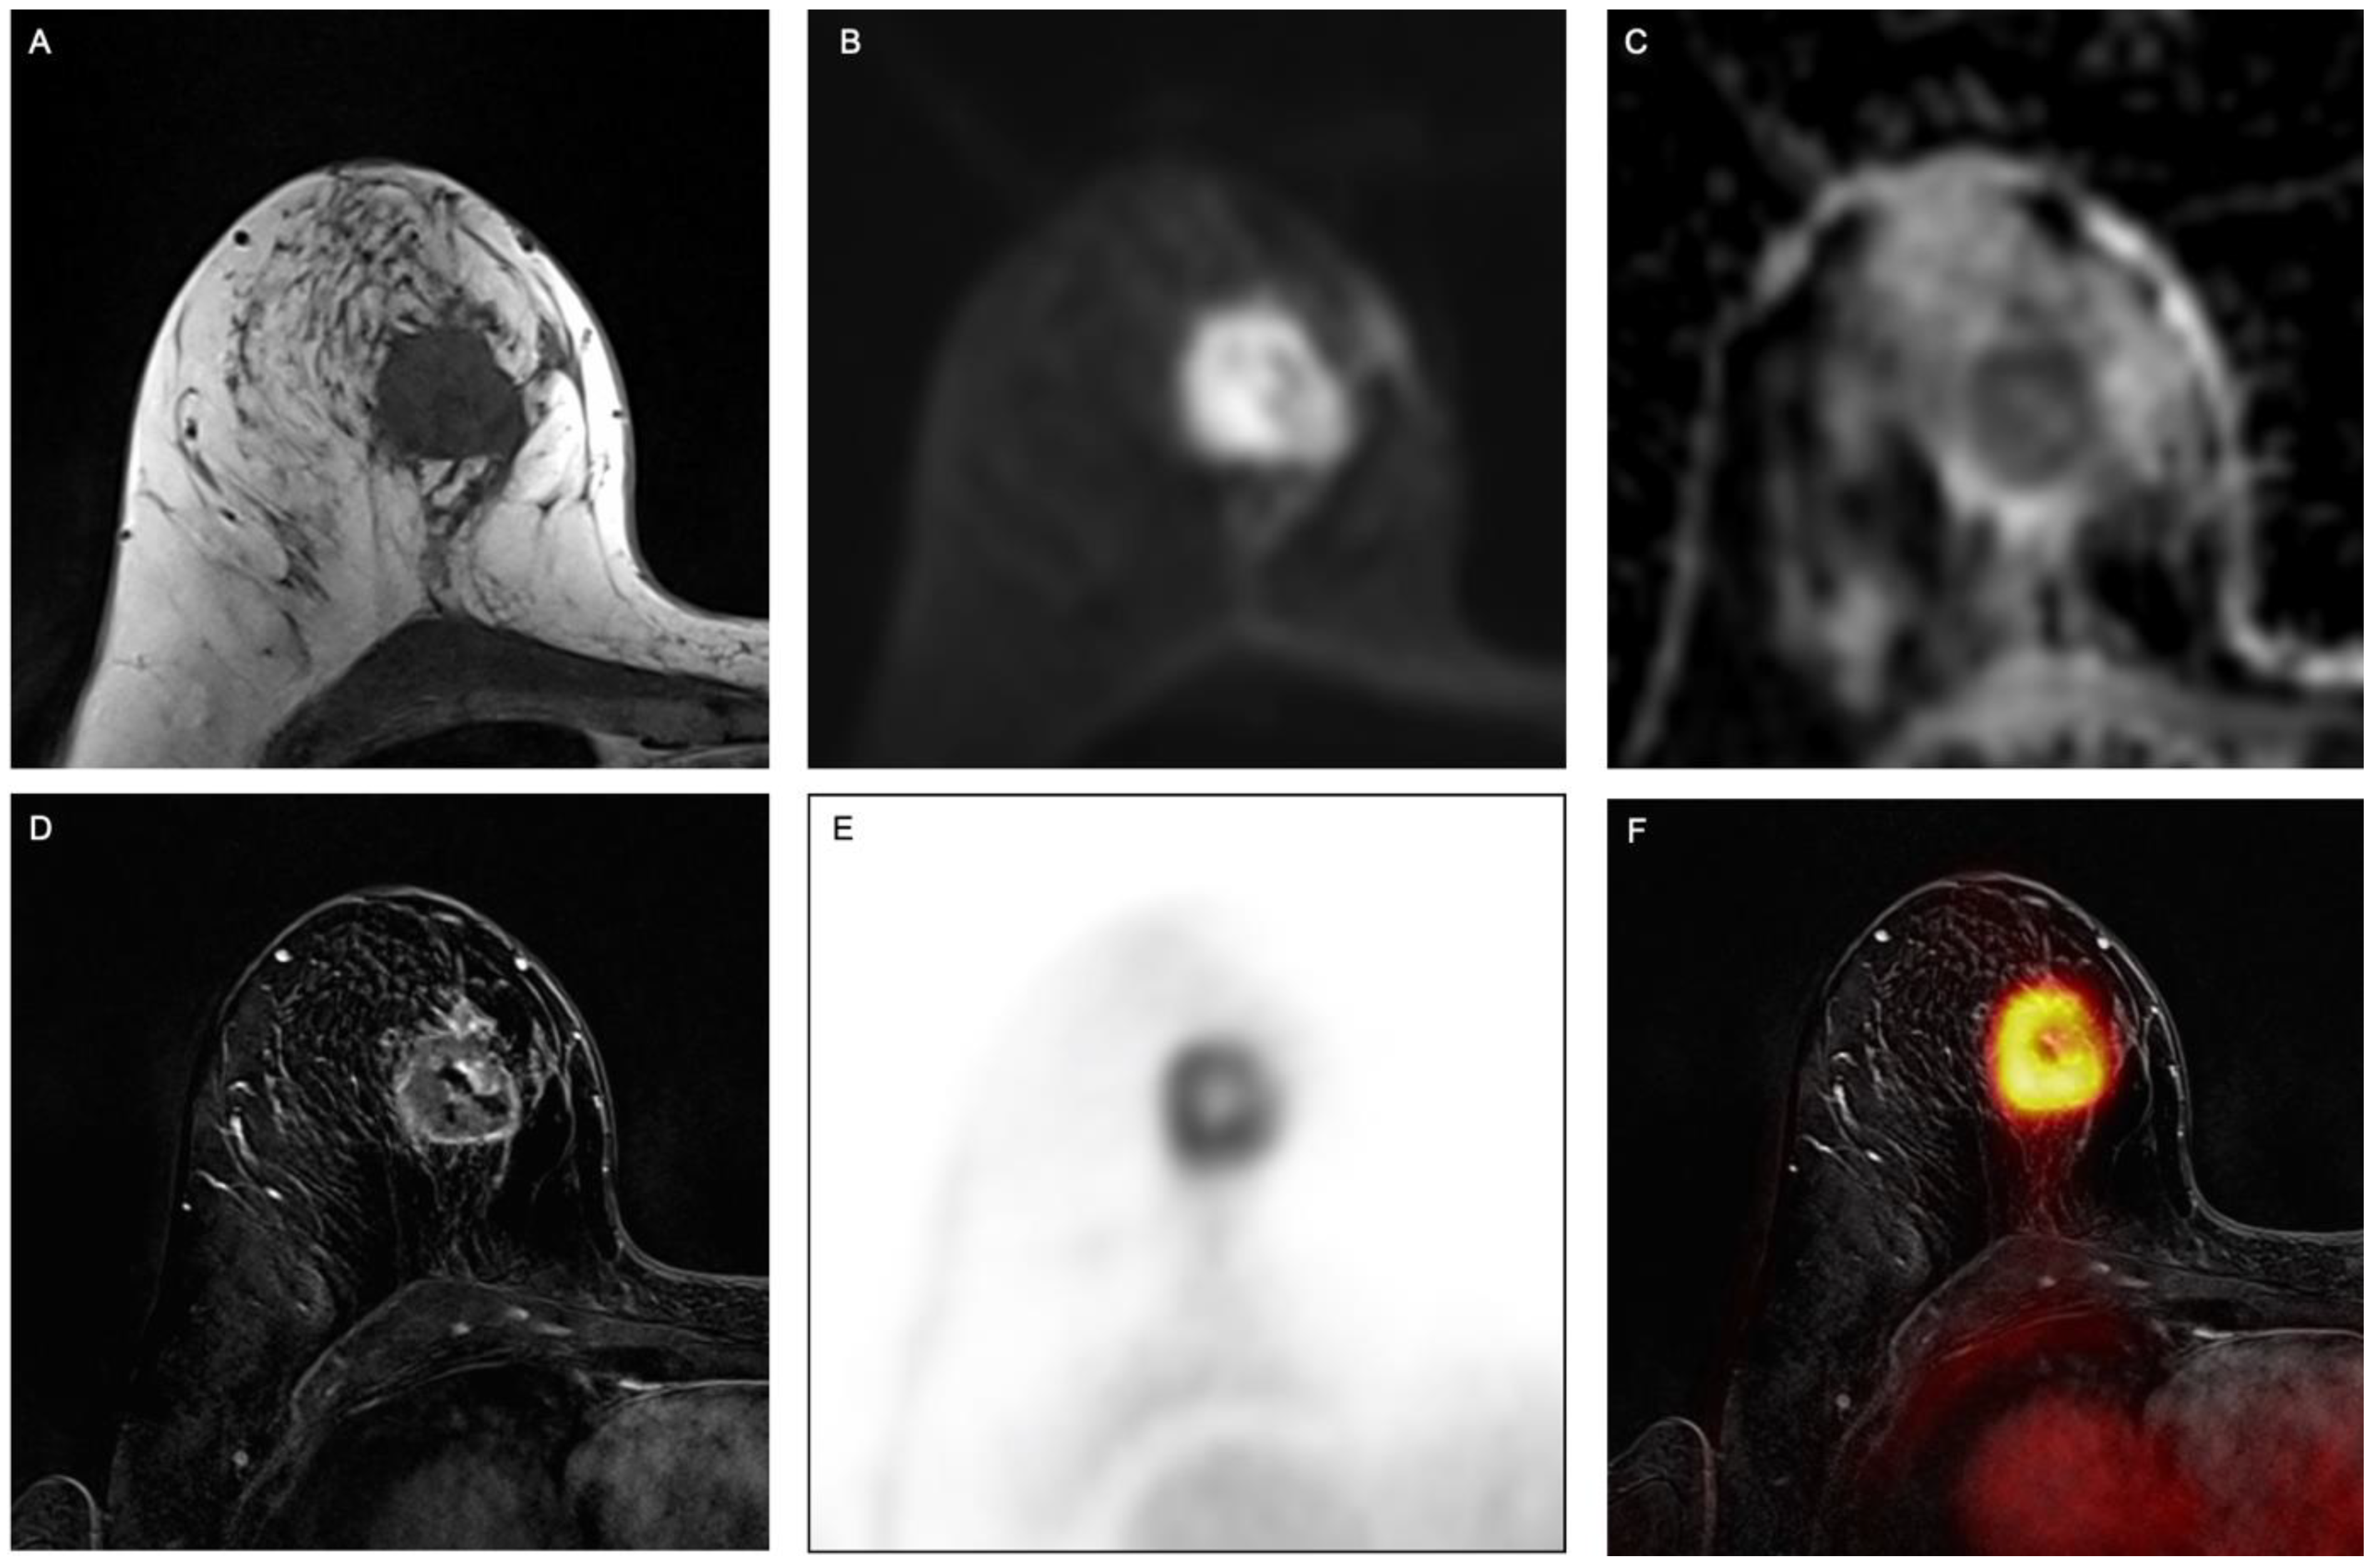

2.2. PET/MRI

2.3. Image Analysis